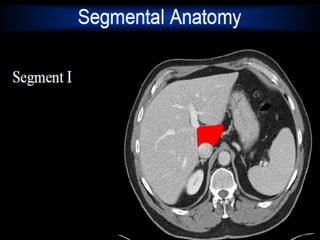

Liver:

 Lies mostly in the

right

hypochondrium, and

protected by rib

cage.

 Divided into two

lobes of unequal size

by the falciform

ligament.

3/22/2024 17